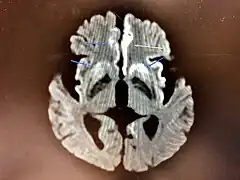

Magnetic resonance image of sporadic CJD[2]

Through the image of MRI, the obvious precipitation of prion protein in the brain is visible.